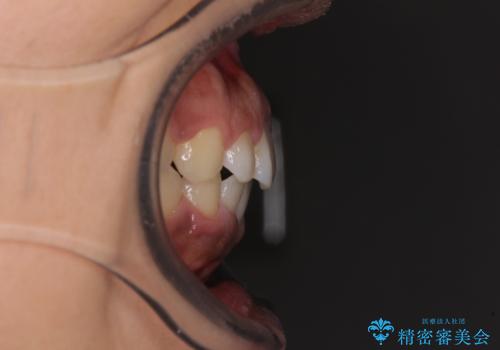

- 上下前歯の叢生を気にして来院された患者様です。

当初はインビザラインにて治療を開始しましたが、自己管理による治療が難しくなり、ワイヤー矯正へ転換して継続しました。